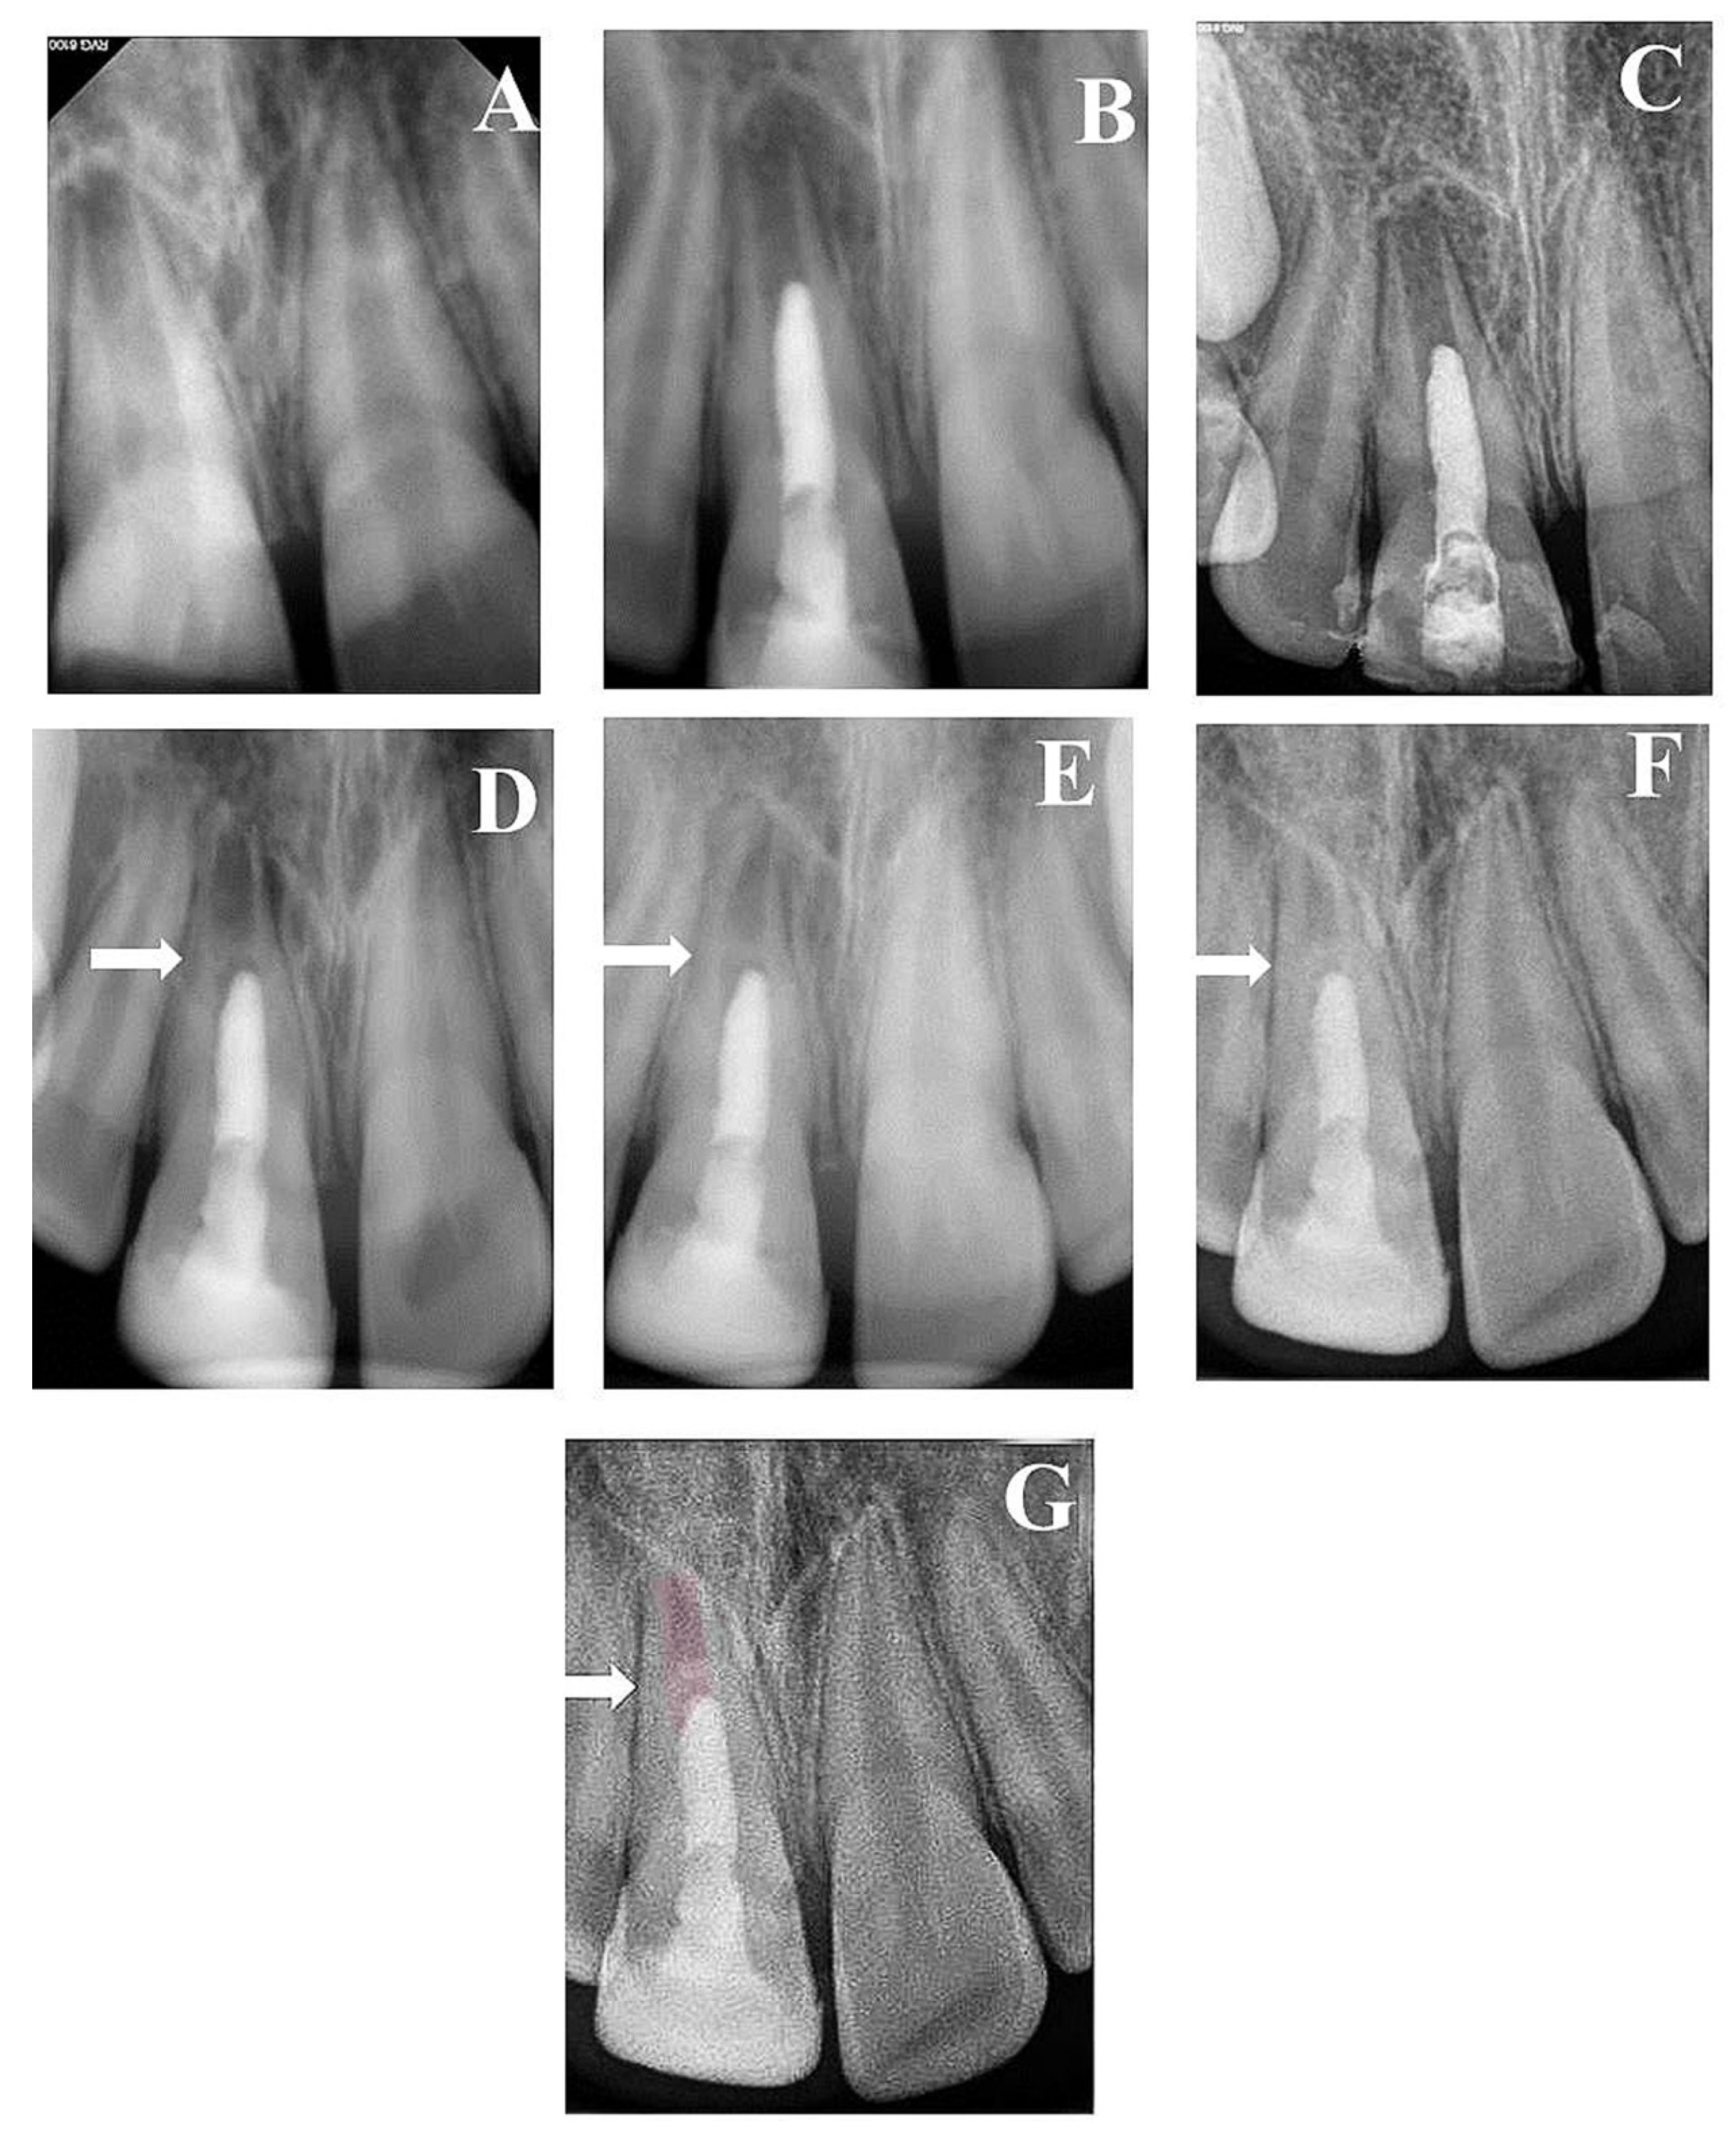

| Follow-Up Time | Median at Each Follow-Up Time (mm) | ||

|---|---|---|---|

| Root Length | Apical Canal Width | Dentin Wall Thickness | |

| Preoperative | 10.36 | 1.14 | 0.48 |

| 6th Month | 10.47 | 1.15 | 0.72 |

| 12th Month | 10.64 | 1.28 | 0.74 |

| 2nd Year | 10.79 | 1.29 | 0.76 |

| 3rd Year | 10.92 | 0.65 | 0.86 |

| 8th Year | 11.4 | 0.24 | 0.98 |